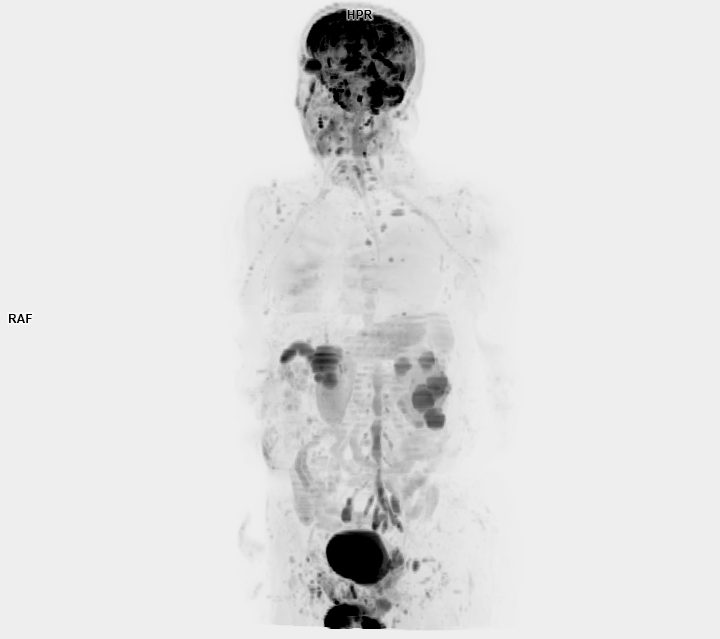

• 3 TESLA MR ÇEKİM GÖRÜNTÜLERİ

3 Tesla MR Çekim Görüntüleri

• 3 Tesla MR Çekim Görüntüleri